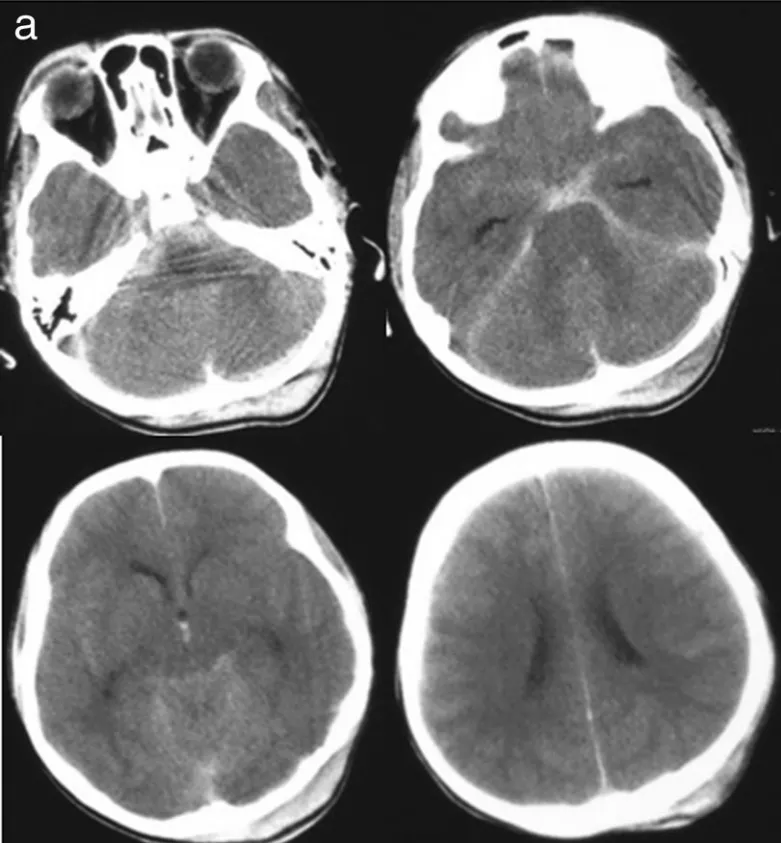

47歲的陳先生在家中突然感到劇烈頭痛,隨即陷入昏迷。家人緊急送醫(yī)后,急診CT檢查給出了令人揪心的結(jié)果:彌漫性蛛網(wǎng)膜下腔出血(圖A),而進(jìn)一步的血管造影揭開了真兇...... CT顯示彌漫性...